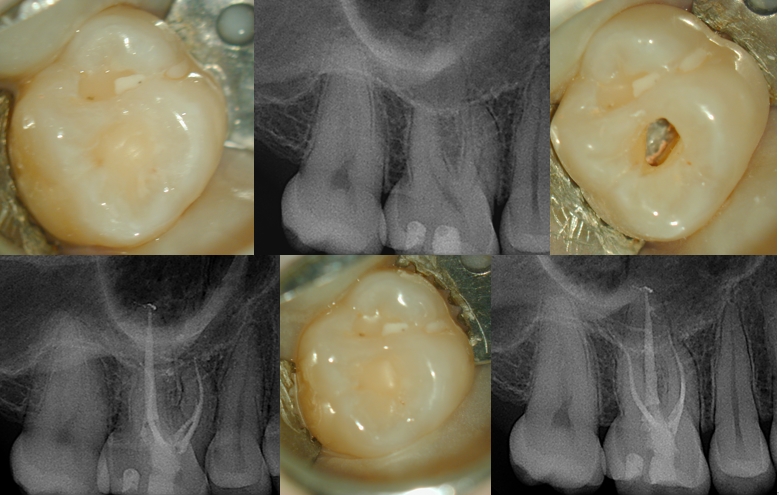

It sounds like you’re describing a fairly typical post-operative sensitivity scenario after replacing amalgam restorations with composite, followed by routine endodontic treatment. Sensitivity to hot and cold is greenskyonlinecom common after composite placement because of factors like polymerization shrinkage, marginal adaptation, or transient pulpal inflammation.